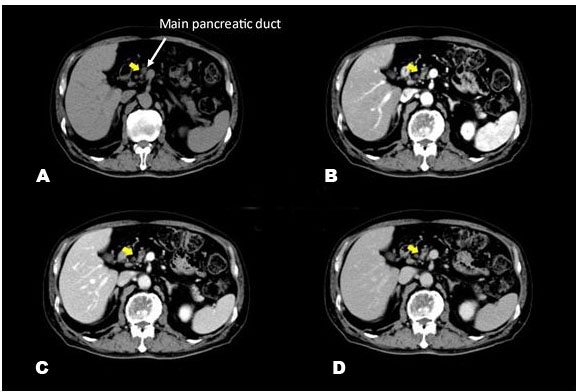

A blood test revealed increases in HbA1c and carcinoembryonic antigen to 11.2% and 8.7 ng/mL, respectively. Abdominal ultrasonography and Sonazoid® (Daiichi-Sankyo, Tokyo, Japan; GE Healthcare, Milwaukee, WI, USA) enhanced ultrasound (Figure 1) did not reveal a hypoechoic figurine indicative of pancreatic cancer on the pancreatic head side of the dilated main pancreatic duct. In the horizontal-section image of the contrast-enhanced CT arterial phase (Figure 2), a tumor suspected to be typical of pancreatic cancer that was contrasted late on the pancreatic head side of the interrupted main pancreatic duct, could not be recognized. In the coronary image (Figure 3), the pancreas was atrophied from the body to the head and there was dilation of the main pancreatic duct, revealing prominent fatty change in the pancreatic body; however, no neoplastic lesion was detectable (Figure 4). Endoscopic ultrasonography (EUS) revealed dilation of the main pancreatic duct and atrophy of the pancreas as on the abdominal ultrasonography; nevertheless, the tumor could not be clearly visualized. Therefore, histological diagnosis using endoscopic ultrasound-guided fine-needle aspiration (EUS-FNA) was considered difficult. Hence, we decided to conduct a detailed examination using other modalities.

Figure 2: Pre-contrast (A), arterial phase (B), portal phase (C), and venous phase (D) images of the abdominal contrast-enhanced CT (computed tomography) at the first visit are shown. No tumor-causing obstruction was visualized on the pancreatic head side of the dilated main pancreatic duct, and soft tissue exhibiting a contrast enhancement effect similar to that of normal pancreatic tissue was observed (yellow arrow).